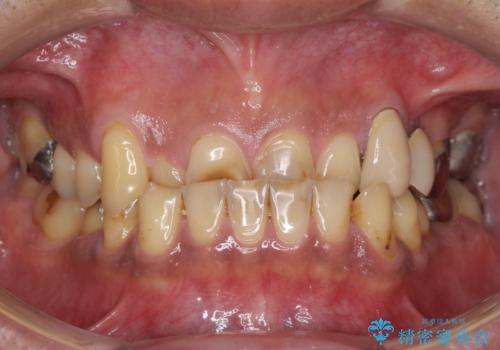

外れるブリッジと気になる八重歯 総合歯科治療で美しい口元に

歯周病 、インプラント、 矯正 全顎治療